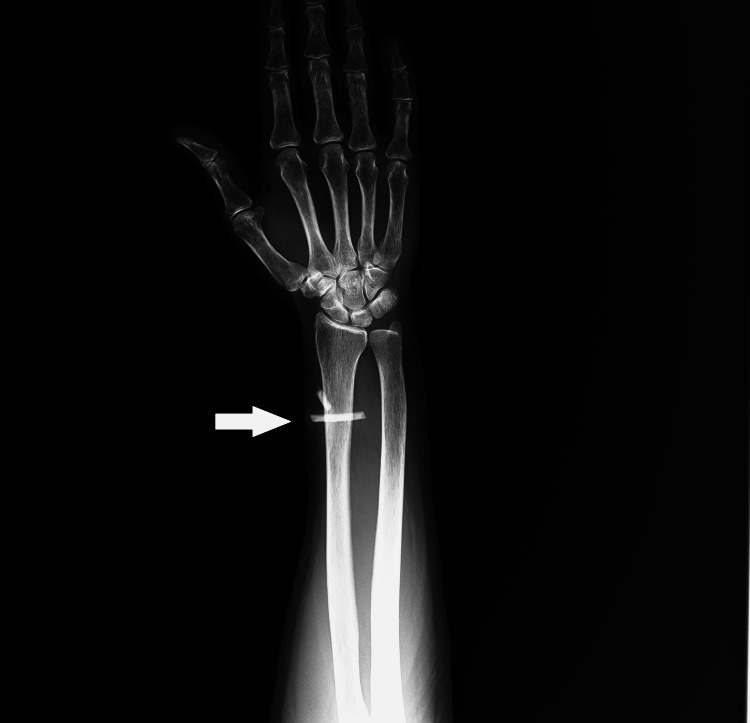

On X-ray, two radio-opacities were noted in the left distal forearm over the distal radius. This was consistent with broken fragments of a bangle in the subcutaneous plane (Figure 4).

Figure 4. X ray image showing bangle pieces in distal forearm (arrow).

On correlating the findings of both ultrasound and radiograph, the diagnosis of retained pieces of foreign body in the soft tissue of the left forearm was confirmed.